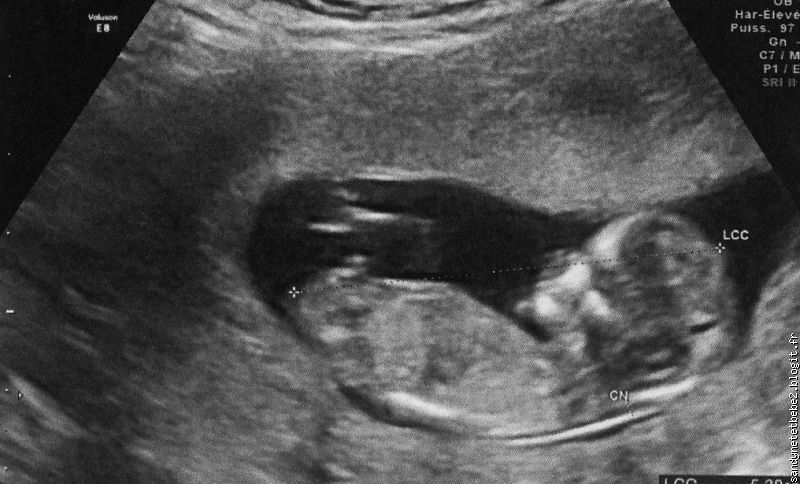

Première échographie

| première écho |

Mardi 11 mai 2010

Autre grand évènement pour nous trois après le test de grossesse positif, la première échographie. On est tous excité car cela fait un moment qu’on attend ce jour pour savoir si tu vas bien.

Nous avons emmené ton grand frère avec nous car c’est un moment que nous voulons également partagé avec lui. Il est très impatient de te voir dans mon ventre. Depuis le temps qu’on lui parle du « bébé dans le ventre à maman.

Dès qu’il a vu le gynéco, c’est la première chose qui lui a demandé : « je veux voir le bébé dans le ventre à maman ».

Il était très content et nous aussi. Tout va très bien. Tu es bien tout seul dans mon ventre. Tu bouges bien. On est rassuré, c’est ton papa qui va peut être arrêté de me faire des cauchemars de toi la nuit car il avait trop peur qu’on nous annonce une mauvaise nouvelle. Ah ces hommes…..

Je l’ai donc appelé dans la soirée ; je lui ai demandé si son ordi été allumé car j’avais un mai à lui envoyé et qu’il fallait qu’elle l’ouvre tout de suite. Ce mail, c’était les photos de l’échographie que nous avons passé aujourd’hui.